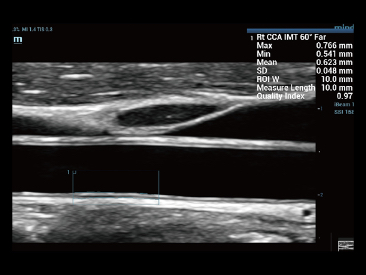

Oprócz uzyskiwania jako?ci obrazu typowego dla aparatów klasy premium, Resona 7 rozszerza mo?liwo?ci klinicznych badań USG dzi?ki rewolucyjnej funkcji V Flow, s?u??cej do oceny hemodynamiki naczyń, a tak?e najlepszej na rynku funkcji inteligentnego, automatycznego uzyskiwania p?aszczyzny na podstawie zestawów danych obj?to?ciowych 3D, umo?liwiaj?cej diagnozowanie stanu Centralnego Uk?adu Nerwowego u p?odu. Aparat Resona 7 ??czy w sobie najbardziej intuicyjn?, wielodotykow? obs?ug? za pomoc? gestów oraz wszystkie kluczowe funkcje kliniczne, co sprawia i? jest prawdziwym liderem we wprowadzaniu innowacji w ultrasonografii.